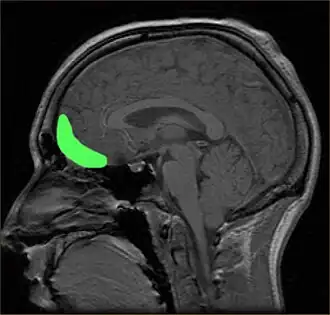

Research using EEG scans discovered that emotion centers and reward centers in the brain lit up when participants viewed images of baby animals, and that emotions were stronger for animals perceived as more cute.[11] Specifically, activity in the orbitofrontal cortex (an area associated with emotion and pleasure) increases,[12] as quickly as one-seventh of a second after seeing a baby face.[13]

The hormone oxytocin (often called the "cuddle hormone" or the "love hormone") is produced in the hypothalamus in the brain and released into the bloodstream by the pituitary gland upon seeing something cute and neuropeptide surges contribute to feelings of affection.[17][18] Vasopressin is also produced in the hypothalamus and released from the posterior pituitary in the brain. When released it compels the individual to protect and defend what is considered vulnerable. Many mammals, such as grizzly bears, will display aggressive behaviour to protect their young.[19]

A more recent study conducted by Stravropoulos and colleagues in 2018, used electroencephalography (EEG) scans to investigate brain activity during cute aggression experiences. Fifty-four participants rated their reactions to baby animal images comparing these to adult animals. Higher ratings were given after viewing baby animals and the EEG analysis found in the N200 component, emotional responses peaked around 200 ms after stimulus onset. Participants who reported higher levels of cute aggression showed a stronger reward processing response in the mesolimbic system. The involvement of emotional and reward processing in the brain enables insight to the underlying mechanisms of cute aggression.[27]